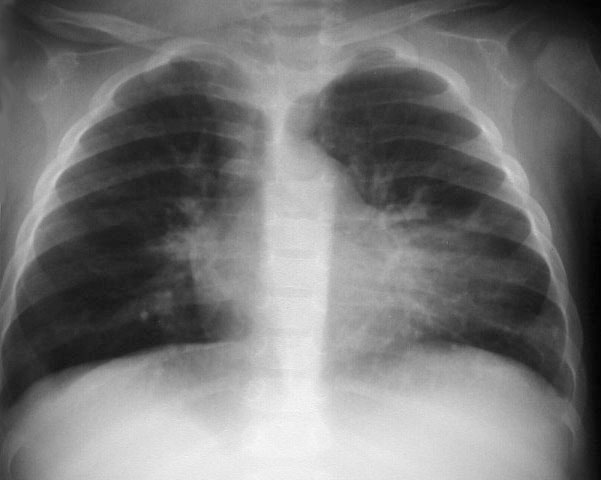

SIGNO DEL TUMOR FANTASMA O TUMOR EVANESCENTE

Signo que describe al derrame pleural atrapado en la cisura menor, especialmente en pacientes con insuficiencia cardiaca. El derrame loculado en la proyección posteroanterior se ve como una lesión nodular o masa que simula un tumor sólido (imagen superior). Sin embargo, la evolución rápida hacia la desaparición de esta lesión sugiere que se trata de derrame.

Vemos en las imágenes un tumor fantasma que desaparece en el control realizado cinco días más tarde.

En la primera imagen, la presencia de derrame pleural asociado y el engrosamiento del resto de la cisura menor, visible como una línea superpuesta al tumor fantasma, sugieren el diagnóstico.